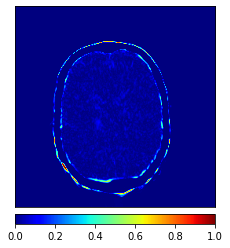

In this paper, we propose a bidirectional learning model, known as dual contrast cycleGAN (DC-cycleGAN), for medical image synthesis from unpaired data. Specifically, a dual contrast (DC) loss is formulated that leverages the advantage of samples from the source domain as negative samples to indirectly build constraints between real source and synthetic images via discriminators, and synthesize images more related to the target domain by enforcing the synthetic images to fall far away from the source domain. In addition, structural similarity index (SSIM) [35] and cross-entropy (CE) [48] are integrated into the DC-cycleGAN structure to avoid disappearing gradient information that is caused by a mean absolute error (MAE) and synthesizing irrelevant images. SSIM considers luminance [35] and CE converges fast as its back-propagation error is less than MSE [28]. As can be seen in Figs. 1 and 2, using SSIM and CE with dual contrast can generate more clear and accurate MR images as compared with that of MAE and MSE, and SSIM and CE without dual contrast loss. Although both SSIM and CE with dual contrast and without dual contrast generate similar CT images, SSIM and CE with dual contrast quantitatively generate better images as shown in Table 4. The experimental results indicate that DC-cycleGAN is able to consider more complex features such as structure in synthesizing images and produce remarkable results as compared with other state-of-the-art methods reported in the literature.

Moreover, Figs. 6 and 7 show the synthesized MR and CT images along with the errors between the real and synthesized images by different methods, respectively. It can be seen that the synthesized images by DC-cycleGAN are more identical to the real ones as compared with other methods. This indicates that effectiveness of SSIM and CE along with dual contrast in synthesizing images. In addition, the error between the groundtruth and synthesized MR/CT images by DC-cycleGAN is relatively less as compared with other methods.

Tables 3 and 4 show the results of MR and CT synthesis, respectively. As can be seen, all components play vital role in both tables. SSIM & CE (w) performs significantly better than other losses in synthesizing MR images. This also can be seen visually in Fig. 1. In contrast, SSIM&CE (w) performs slightly better than SSIM&CE (wo) in synthesizing CT images, both generate more or less similar CT images (see Table 4).